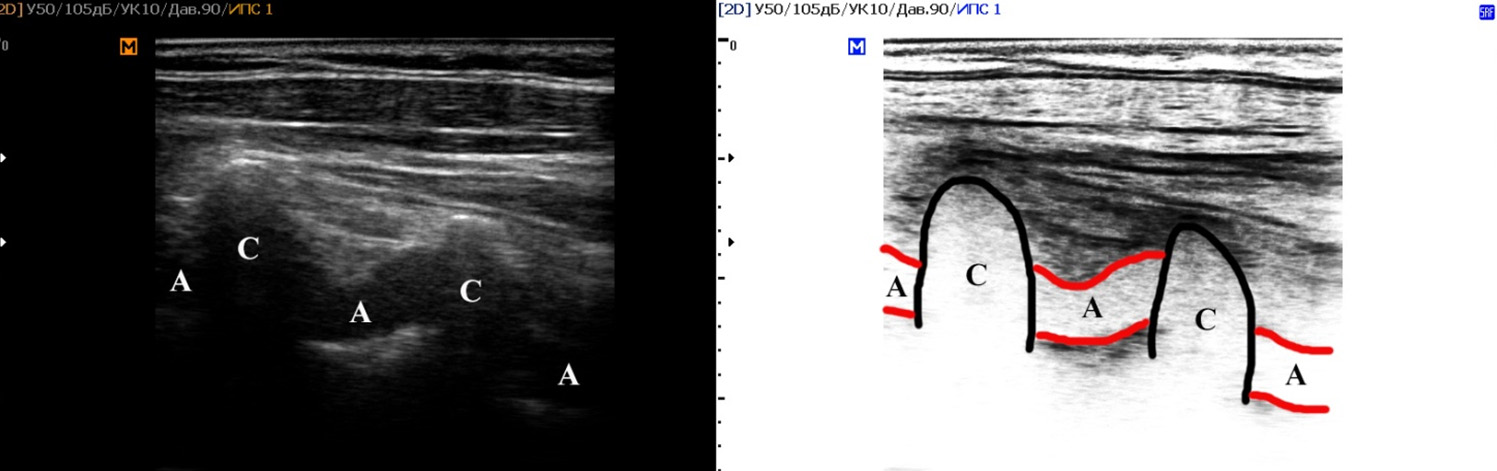

В результате наблюдения без учета стороны визуализации было проанализировано 504 сосудистых комплекса, включавших позвоночные артерии и сопровождающие их вены. Среди женщин было выявлено 146 случаев прямолинейного хода сосудов и 202 случая непрямолинейного хода сосудов (рисунок 1). У мужчин было определено 70 сосудистых комплексов (рисунок 2) с прямолинейным ходом и 86 с непрямолинейным. При оценке статистической значимости данных для всех значений были получены результаты p<0,005 по Стьюденту.

Рисунок 2. Пациент №3 А, мужчина 41 год. Пример визуализации прямолинейного хода сосудов на уровне V2 сегмента позвоночных артерий (SonoAce R7, линейный трансдьюсер).